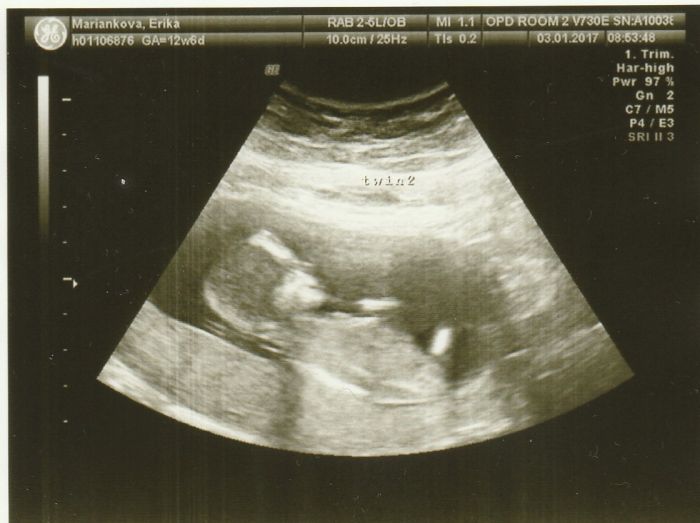

Ohlasujem sa po dlhsom case, nie ze by som nesledovala dianie sa tu ale to cakanie na prvy ultrazvuk a strach.... Takze dnes sme isli aj s drahym na prvy utz v Dubline. Ako som pisala do konca prveho trimestra tu oni nic neriesia, cize to 2 mesacne cakanie

. Podla tehotenskej kalkulacky som mala mat termin na 12.7, po dnesnom utz mi to upravili na 6.7a na moje prekvapenie su tam 2 fazulky

. Prvotny sok a moj drahy skoro nechal oci na obrazovke. Ale zato hned ako sme vysli z nemocnice tak zacal ze musime zacat vymyslat mena a hned radsej 4...2 chlapcenske a 2 dievcenske....uuuf tolko radostiiiiiii...len neviem ako to, lebo ani jeden nemame v rodine dvojcata. krasny vecer a pripajam aj foto...na 1 su obe fazulky a na druhej ten menej hamblivy, asi to bude chlapec